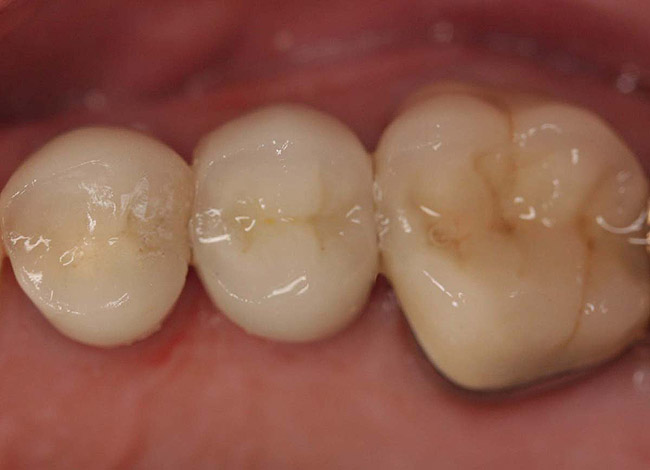

Figure 11  Final porcelain-fused-to-metal crown.

Figure 11